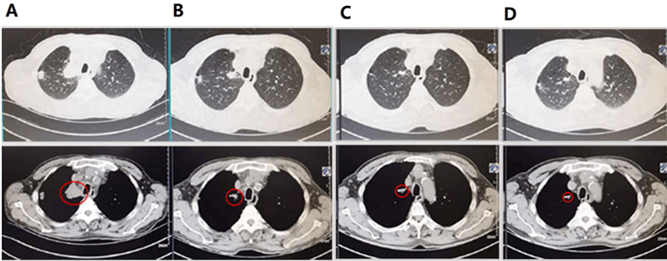

Subsequently, we treated the patient with pembrolizumab as the first line of therapy because of PD-L1 high expression on April 26, 2019. Before treatment, a CT scan was performed (Figure 2A). After one pembrolizumab infusion (200mg/3 weeks), the patient’s voice sound improved, suggesting pembrolizumab may be effective and inhibited tumor growth. After infusion twice, a CT scan was performed. As shown in (Figure 2B), the size of the tumor significantly decreased compared to pre-treatment, resulting in a partial response. After 4 cycles of pembrolizumab treatment, the tumor was getting smaller (Figure 2C).

To date, pembrolizumab treatment for the patient has been continued for about 29 months. He had no obvious clinical symptoms and no severe adverse events. After 41 cycles of pembrolizumab treatment, a CT scan demonstrated that the size of the tumor was tiny compared to pre-treatment, indicating that pembrolizumab was sustained effective (Figure 2D).

Figure 2: The image pre-treatment and after-treatment CT scan. A) Pre-treatment CT scan; B) CT scan after one cycle of pembrolizumab; C) CT scan after two cycles of pembrolizumab; D) CT scan after forty-one cycles of pembrolizumab. Red circles indicate tumors.